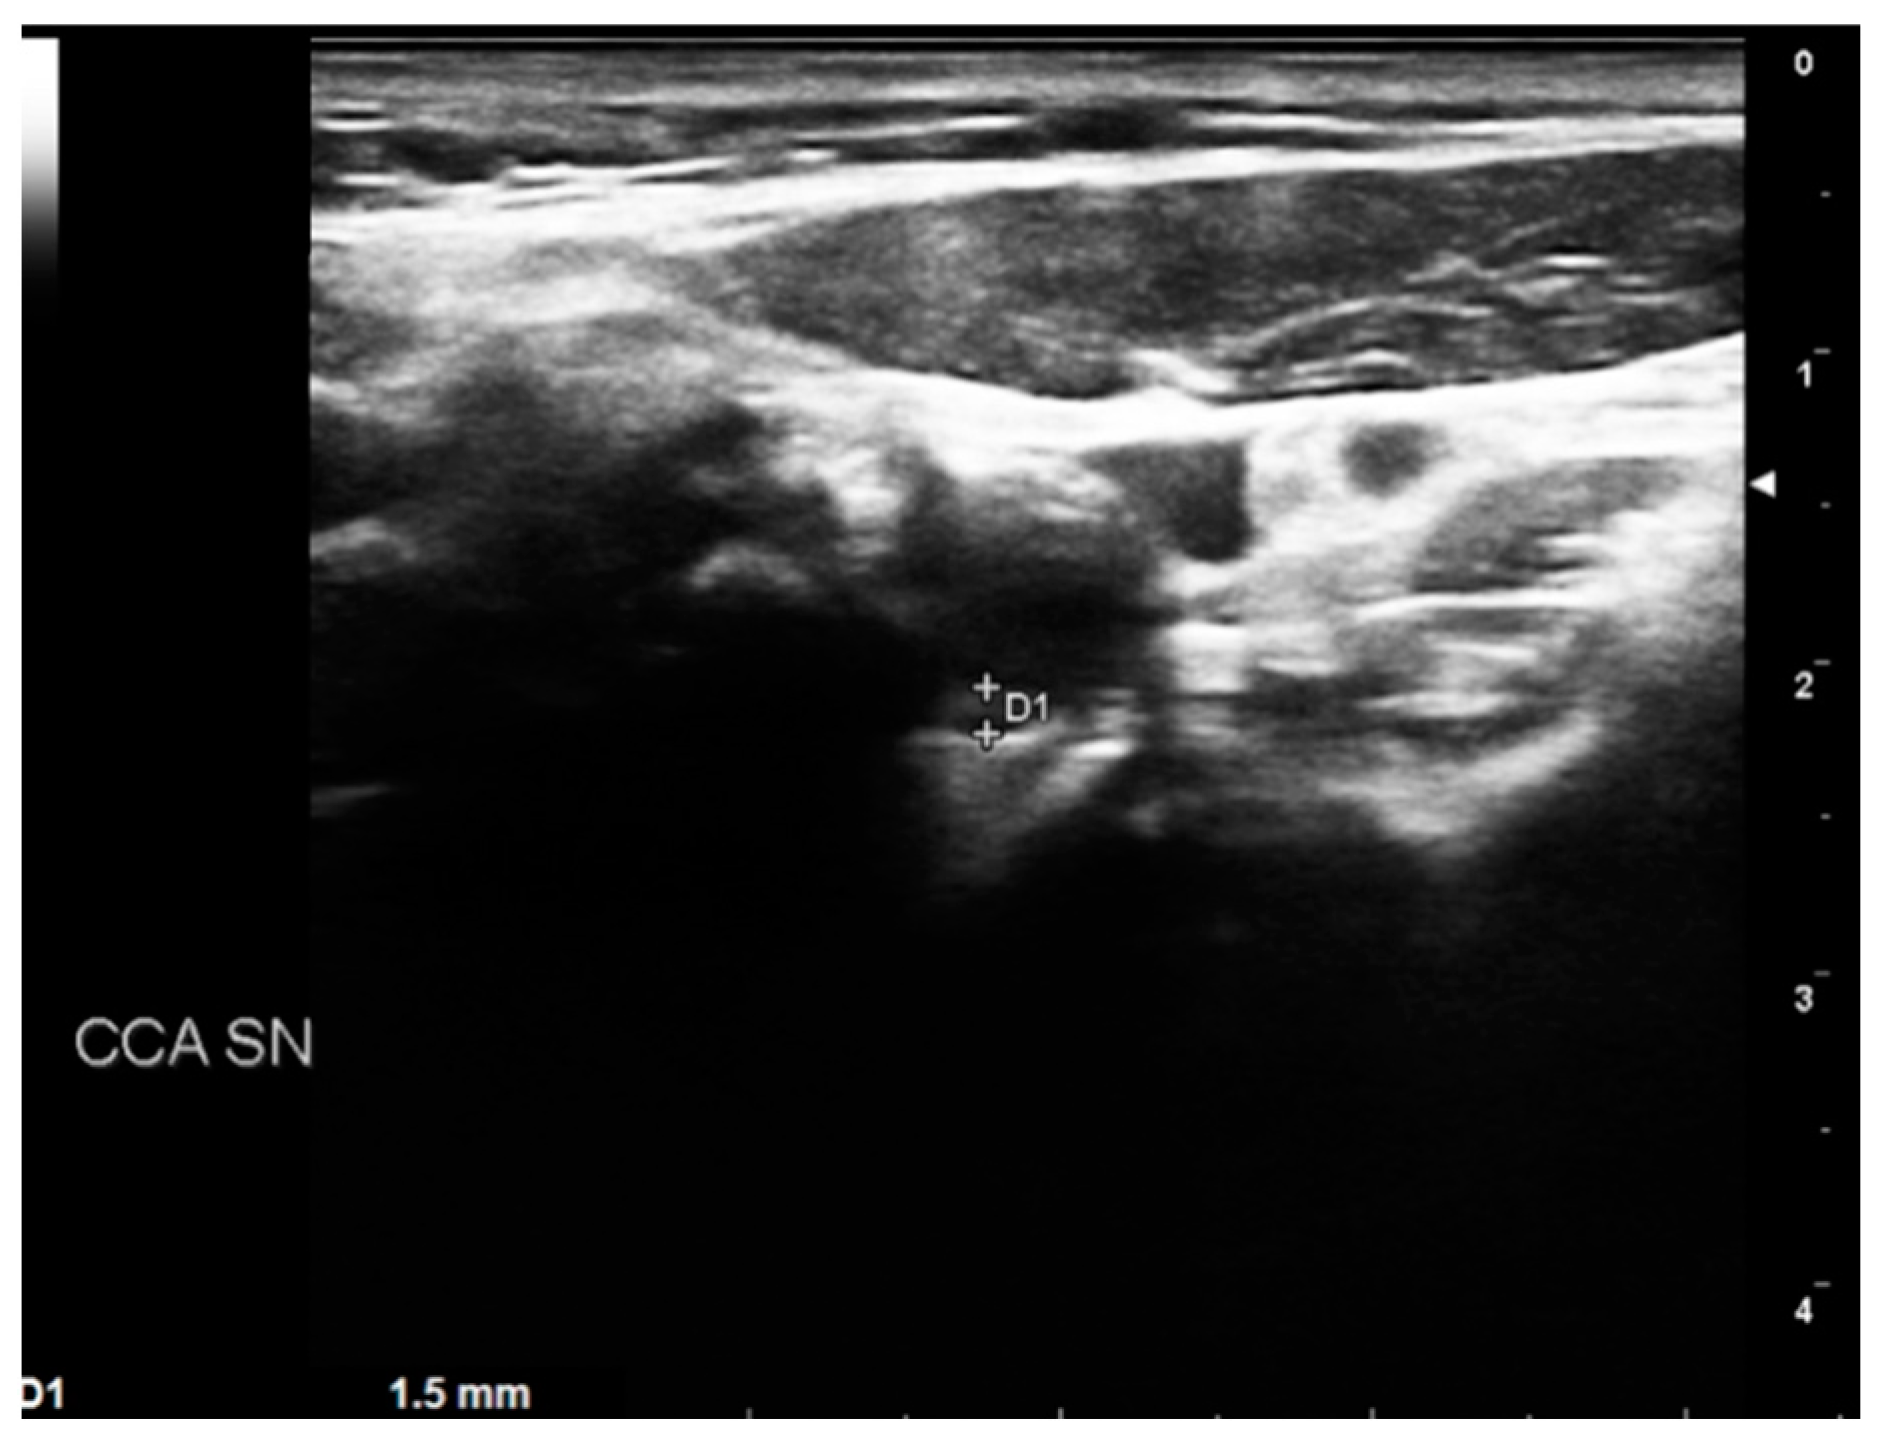

- BORDERLINE: Patients with IMT within the range of 1 mm to 1.5 mm. Here, considering the absence of true plaque but the presence of first modifications in the intima layer, our protocol provided a clinical evaluation with the risk factor identification (Figure 4).

Figure 4. DUS image showing plaque in CCA—BORDERLINE.